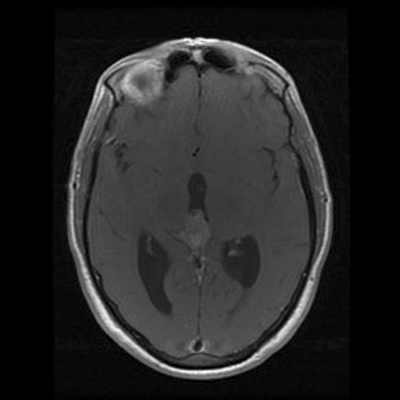

An MRI of the brain with and without contrast revealed a 2.6 x 1.3 x 1.6 cm  (AP x CC X W) heterogenous lesion within the region of the pineal gland and projecting into the third ventricle. The lesion had both solid and cystic components and demonstrated heterogenous enhancement on T1-weighed images. The enhancement is located medial to the veins of Rosenthal, inferior to the cerebral veins, and posterior to the vein of Galen. The mass is isointense to the cortex on T2-weighed images. No significant midline shift or significant edema was observed. The ventricular system was prominent in size, consistent with mild hydrocephalus. Basilar cisterns were preserved and normal cerebrovascular flow-voids were seen.  No abnormalities of the cerebellar or cerebral parenchyma, the brainstem or the cervical spinal cord were observed. Dural venous sinuses and meninges were unremarkable. Regions of the orbit and sella were unremarkable. Paranasal sinuses demonstrated paranasal sinus disease of the bilateral maxillary and left ethmoidal sinuses.

T1+C